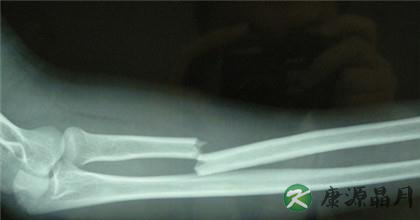

高强度的工作或者是过于剧烈的运动碰撞容易导致骨折、骨裂等情况,比如踢足球如果不懂得保护自己是很容易导致骨折的,下面是对于骨折病人的护理方方面面的叙述,希望可以帮助有需要的朋友。